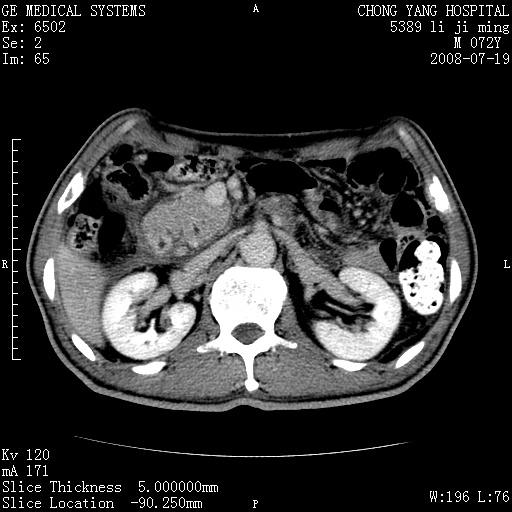

以下是引用zjzjr在2008-7-19 20:57:00的发言:[br]胰头增大,边缘模糊,周围可见渗出影,右侧肾前筋膜增厚.支持胰腺炎.

以下是引用yangyudong333在2008-7-20 6:56:00的发言:[br]胰腺增大尤以胰头明显,边缘模糊,周围可见渗出影,右侧肾前筋膜增厚,肠管於涨.支持胰腺炎

以下是引用不学无术在2008-7-19 23:15:00的发言:[br]胰腺增大尤以胰头明显,边缘模糊,周围可见渗出影,右侧肾前筋膜增厚,肠管於涨.支持胰腺炎